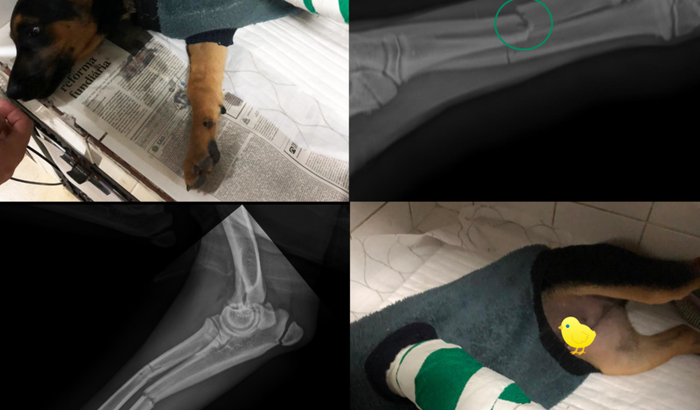

Meu nome é Vitória, e criei essa vaquinha pois preciso arrecadar R$ 2875,00 para pagar uma cirurgia que meu cachorro Mike Tyson de 3 meses precisa realizar. Ele foi atropelado e sofreu uma fratura no osso da perna esquerda, está sentindo muita dor e não consegue andar. Essa situação pegou a mim e a minha família de surpresa e não conseguimos arcar com esse valor, por isso estou pedindo ajuda, só queremos que ele fique bem o mais rápido possível e volte para casa.